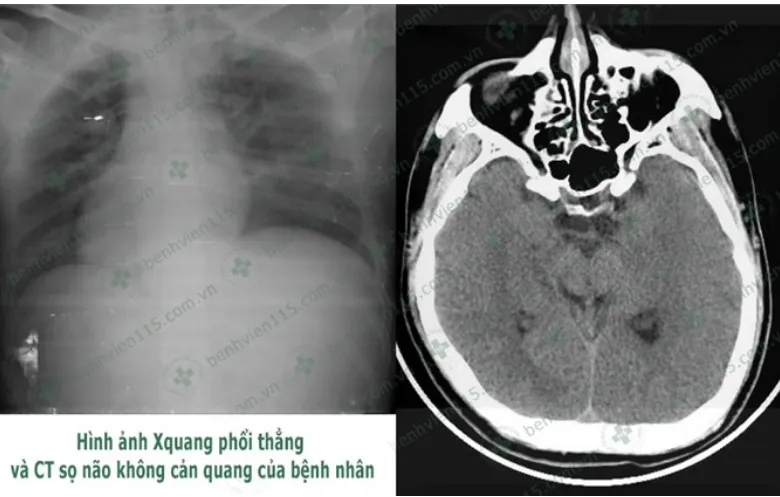

Kết quả chụp CT cho thấy anh N. bị hôn mê sâu. (Ảnh do BV cung cấp)

Các BS chẩn đoán bệnh nhân N. hôn mê sâu do hạ đường huyết kéo dài và bị viêm phổi nặng. Bệnh nhân được hỗ trợ hô hấp bằng máy thở và truyền đường với nồng độ ưu trương để nâng mức đường huyết về bình thường. Tuy nhiên tri giác bệnh nhân vẫn không cải thiện. Các BS tiếp tục điều trị tích cực và tri giác bệnh nhân dần cải thiện. Sau một tuần điều trị, hiện bệnh nhân N. đã tỉnh táo hơn, có thể trò chuyện và nhận biết người thân nhưng rất chậm.